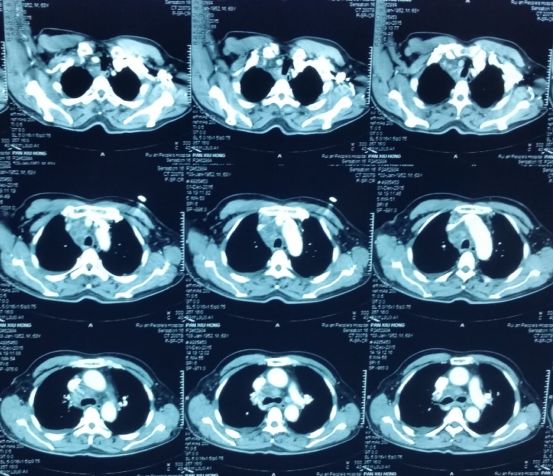

■ 胸部增强CT示:右肺门、纵膈内隆突下、气管前腔静脉后及胸廓入口处多发淋巴结增大,考虑淋巴瘤可能大,两侧少许胸腔积液,两肺下叶少许渗出,右肺中叶少许纤维灶(图1)。

图12015.12.1当地医院胸部增强CT(抗痨治疗前)